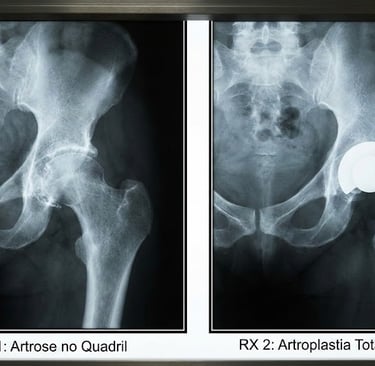

Radiografia (exame principal): mostra estreitamento do espaço articular, osteófitos e alterações ósseas. Geralmente, basta a incidência AP da pelve e perfil do quadril.

Artroplastia total de quadril (prótese): substitui a articulação danificada por implante, aliviando dor e restaurando mobilidade em casos avançados.